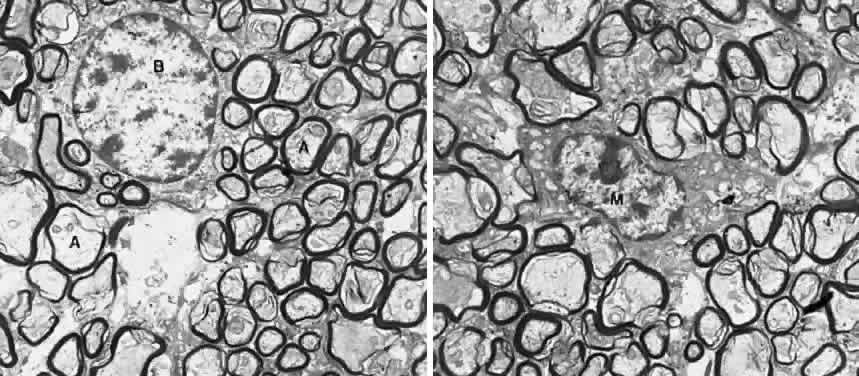

Fig. 3. Ultrastructure of the optic nerve. (A) Axons are surrounded by myelinated sheath. (B) Oligodendritic cell. (M) Microglial cell. × 18,750. (Courtesy of Dr. John R. Guy)

The axons, also called nerve fibers, are the major component of the optic nerve. The nonmyelinated axons of the retinal ganglion cells converge toward and turn sharply on the optic disc. Once they penetrate the lamina cribrosa, the axons immediately become myelinated (see Fig. 2). In cross-section using hematoxylin and eosin (H&E) stain, the principal myelinated optic nerve fibers appear as small, faintly stained, eosinophilic dots surrounded by relatively clear halos. These clear halos, representing the myelin sheaths, are the result of lipid dissolution during processing. Special stains can be used to enhance the appearance of axons (e.g., Bodian's method and Luxol fast blue staining). Under electron microscopy, the nerve fibers are identified as cytoplasm with mitochondria enveloped by multilaminar myelin sheaths. The myelin sheaths of the optic nerve are formed by oligodendrocytes (Fig. 3). A distinct arrangement of axons is found in the optic nerve: the peripheral retinal axons are located in the peripheral portion of the optic nerve, and the central area of the nerve contains fibers from the posterior retina. Macular fibers form the papillomacular bundle and enter the disc temporally; they remain temporal for a short distance behind the eye, but as they proceed further posteriorly these fibers become diffusely distributed. Nerve fibers arising in the nasal half of the retina cross in the chiasm; axons arising in the temporal half are uncrossed.11 It is believed that most optic nerve fibers carry afferent visual and pupillomotor impulses. A few fibers project to the hypothalamus or superior colliculus, where they may provide afferent information affecting the body's circadian rhythm or a rudimentary representation of the visual space (blindsight), respectively.12,13 Efferent (centrifugal) fibers of the optic nerve, presumed to be vasomotor in function, were identified in the human optic nerve after enucleation of the globe. Silver staining of these axons showed retrograde degeneration, whereas the remaining axons in the orbital portion of the optic nerve showed little or no retrograde degeneration. In uninterrupted optic nerve, efferent axons could not be differentiated from those of the afferent type.14

When viewed by electron microscopy, oligodendrocytes appear moderately electron dense compared with astrocytes. The nucleus is round or oval and is usually eccentrically located, leaving a large mass of cytoplasm at one pole of the cell. The nuclear content exhibits a slight clumping of chromatin that appears as a rim beneath the nuclear envelope. The cytoplasm is rich in ribosomes, either free or associated with the endoplasmic reticulum. The Golgi complex is well developed. The oligodendrocytes have neither glycogen granules nor bundles of intermediate filaments (see Fig. 3). When analyzed by immunohistochemical methods, oligodendrocytes stain negative for GFAP but positive for galactocerebroside, myelin basic protein, and neural cell marker HNK-1/N-CAM.5

MICROGLIA. Microglia are the phagocytes of the CNS. In the normal optic nerve, these cells are ordinarily present in small numbers, and most are found within bundles of axons, with some situated adjacent to the glial septa and to blood vessels.17 Normally, these cells are irregularly oval, containing small nuclei and many long and slender branching processes. Under electron microscopy, microglial cells have small, heterochromatic nuclei. The cytoplasm shows vacuoles, granular endoplasmic reticulum arranged in long, narrow strands, and various inclusions, including large dense bodies, lamellar bodies, myelin bodies, and other forms of cellular debris (see Fig. 3).17 Immunohistochemical studies reveal that microglia in the retina are positive for Griffonia simplicifolia B4-isolectin, CR3 complement receptor, leukocyte common antigen (CD45), and antimacrophage marker CD68 (Fig. 5).22,23 These cells do not contain glial filaments.